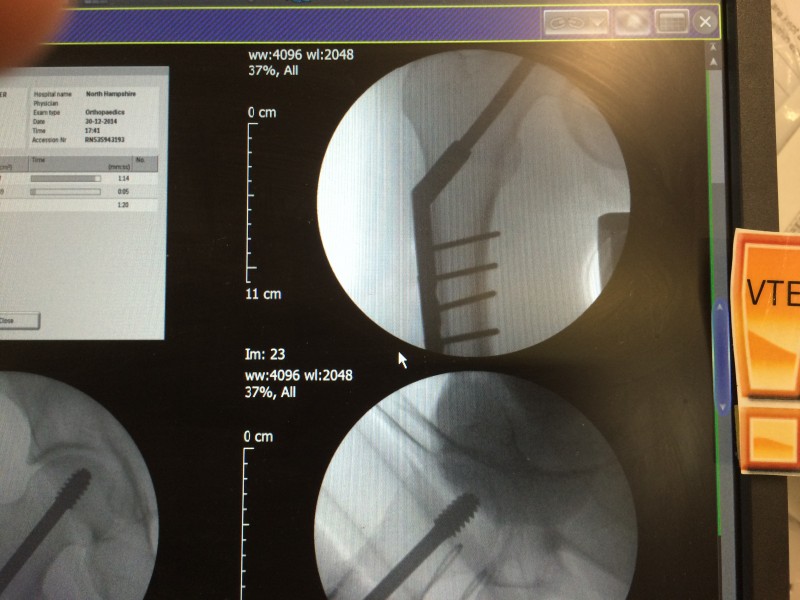

Had the surgery last night and now have a Dynamic Hip Screw fitted. Look it up for the details.

And some x Rays for the medically inclined. If it doesn’t upload from my phone I’ll put them up from home later.

Home now and a new set of challenges. But first some X-Ray porn…

[caption id="attachment_32048" align="alignnone" width="800"] The plate and pins go down the femur. They told me it was a small cut but it looks about six inches long under the dressing.[/caption]

The plate and pins go down the femur. They told me it was a small cut but it looks about six inches long under the dressing.[/caption]

[caption id="attachment_32049" align="alignnone" width="800"] The upper part is threaded and the lower part below the break is unthreaded so the bone can move a little. Press-fit bones mend stronger apparently.[/caption]

The upper part is threaded and the lower part below the break is unthreaded so the bone can move a little. Press-fit bones mend stronger apparently.[/caption]